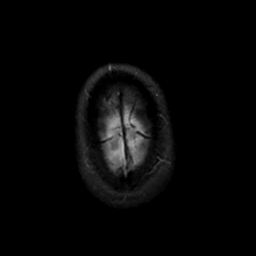

MR Study #18, July 21, 1991 -- Slice #47

[Home][Help][Clinical][Tour 1][Tour 2] Slice 47